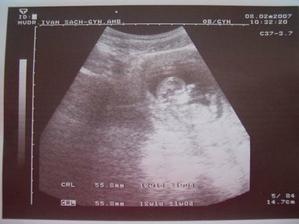

SRPŇÁTKA 2007 - fotky UTZ

album věnované mimískům, které se narodí v srpnu 2007 a jejich maminkám ze "Společného termínu SRPEN"